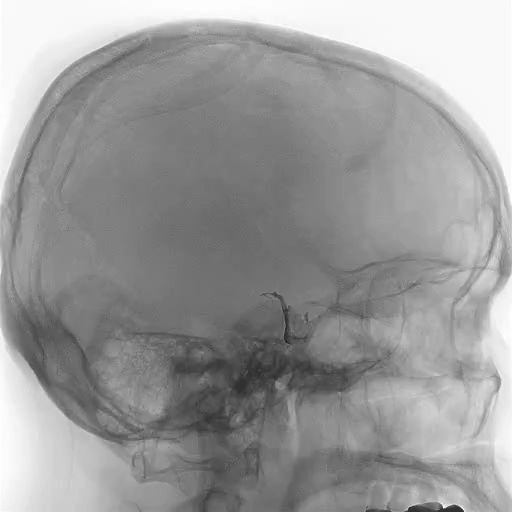

术前CT

DSA-R-ECA-脑膜中动脉

DSA-R-MCA-颞前动脉

DSA-R-VA-颞叶下动脉

●术前诊断:右颞底面AVM

供血动脉:R-ECA-MMA供血畸形团底面

R-颞前动脉供血畸形团前方

R-颞叶下动脉供血畸形团后、下方

回流静脉:直窦(主回流),深部引流

R-Labbe静脉,浅部引流